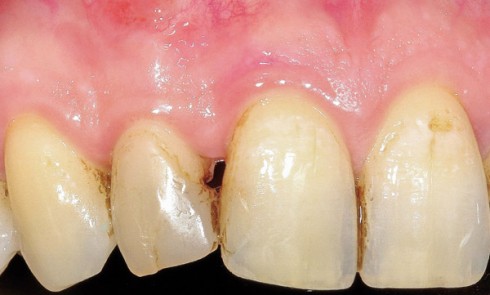

Article réservé à nos abonnés Composites directs : polissage et texture de surface

1. Situation initiale. Le composite a été refait trois fois durant les deux dernières années, du fait de décollements répétés....